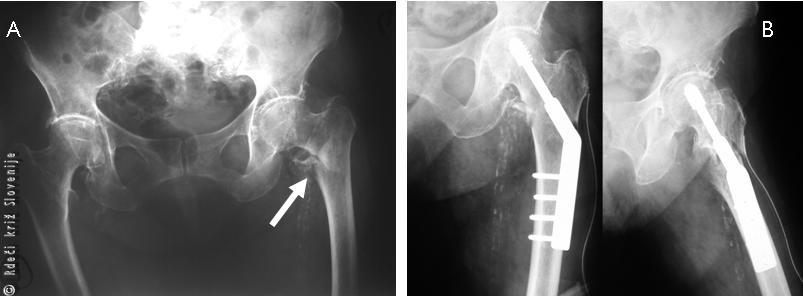

Slika 3

A, B – Pri zlomu stegnenice se spodnji ud zvrne navzven.

A, B – RTG slika zloma zgornjega dela stegnenice in RTG sliki po osteosintezi.